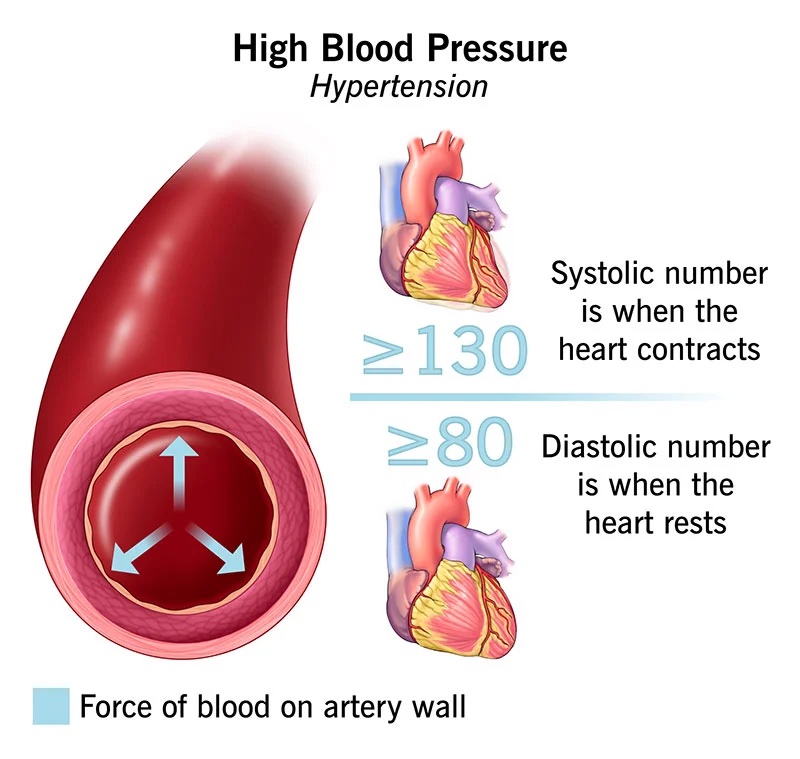

What To Know About High Blood Pressure As You Age National Institute

https://www.nia.nih.gov/sites/default/files/2023-01/high-blood-pressure-aging.png

High Blood Pressure Hypertension Texas Heart Institute

Why Does Systolic Blood Pressure Increase With Age Increased Systolic